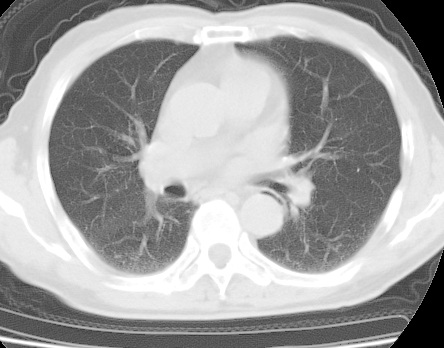

标题: CT24032:男65岁,咳嗽,吸烟20余年,无发热,咳痰 [打印本页]

标题: CT24032:男65岁,咳嗽,吸烟20余年,无发热,咳痰

考虑右肺中叶不张,请大家发表意见

右肺中叶不张、肺门轮廓增大,占位不除外;建议增强,必要时支气管镜详查。

右肺中叶支气管闭塞,中叶肺不张,右侧肺门见肿块影。中心型肺癌的可能大。建议支气管镜检查。

右中叶体积明显缩小,且其支气管未显示,先考虑:中心型肺癌班右中叶肺不张。

建议:支气管镜检查。